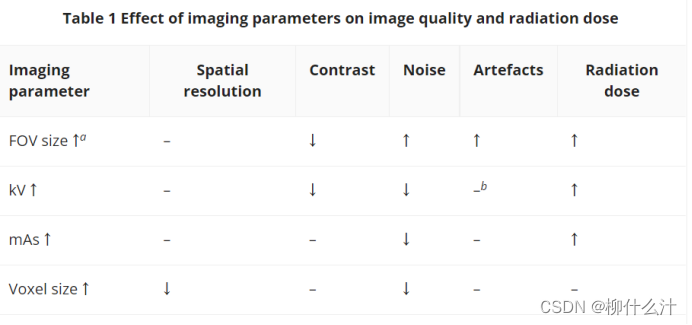

表1显示了成像参数(即kV、mAs、FOV大小和体素大小)与图像质量参数(空间分辨率、对比度、噪声和伪影)以及辐射剂量之间的关系。在优化方面,最直接的成像参数是FOV大小,因为较大的FOV会增加病人的辐射剂量。此外,较大的FOV增加了到达检测器的散射辐射的相对数量,导致噪声和伪影的增加。另一方面,小直径的FOV增加了 "局部断层 "或截断效应,这是因为FOV外存在不对称的质量影响了投影数据(即对于那些穿过有关质量的光束角度)。由于重建算法不能完全补偿这种效应,它可能导致各种图像畸变,如阴影(即向图像的一侧倾斜变暗)和截断伪影。然而,局部断层效应主要影响灰度值的定量使用,无论如何,这往往不是CBCT性能的一个关键组成部分。因此,FOVs应始终保持尽可能小,只覆盖ROI。

↓,减少;↑,增加;FOV,视野;kV,管电压;mAs,管电流-曝光时间积。

a由于没有考虑到光束发散和FOV的截断等因素而产生的微小的图像质量影响。

b在较高的电子管电位值下,光束硬化程度有所降低

尽管千伏和毫安具有相似的整体效果,但它们之间有一个重要的区别。这两个因素,当增加时,主要是增加辐射剂量和减少噪音,因为发射的X射线总量增加。相应地,对比度-噪声比也会增加。在优化方面,应根据所需的图像质量和病人的大小来选择kV和mAs水平,确保图像质量足以满足特定的成像任务,并尽可能降低剂量。然而,千伏的影响更加错综复杂,因为它还影响到探测器的探测效率和X射线散射的相对贡献,等等。鉴于X射线相互作用(吸收和散射)的数量和性质随X射线能量的变化而变化,对比度和剂量都受到影响。在固定的剂量水平下,牙科CBCT的最佳千伏设置取决于成像任务(例如,高对比度细节或低对比度软组织的可视化),尽管最近对某种CBCT模型的研究表明,考虑到60-90千伏的范围,在相同的剂量水平下,增加千伏会导致更高的对比度-噪声比40。

严格来说,改变体素大小并不影响辐射剂量,因为这是一个可自由调节的重建参数。较大的体素尺寸会以图像清晰度为代价降低噪音,反之亦然。在实践中,一些制造商执行预先设定的 "分辨率 "协议,较小的体素尺寸对应较高的mAs值,以保持噪声相对稳定。